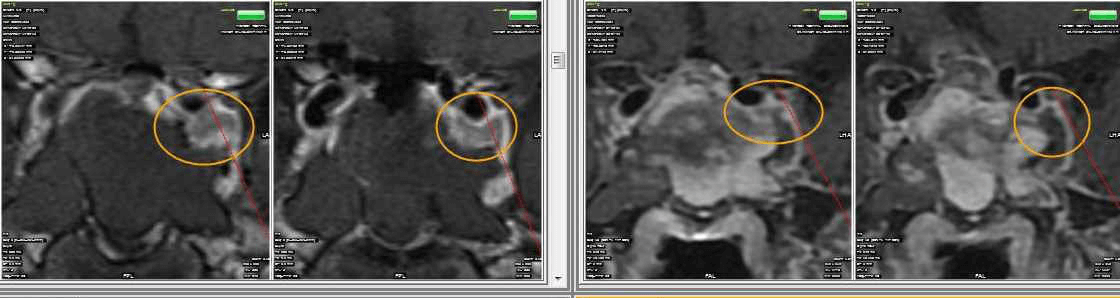

65 year old male with Pituitary Macroadenoma with cavernous sinus extension. Endoscopic Transsphenoidal Surgery done with Intraoperative MRI showing residual tumor in the cavernous sinus region under the left carotid artery. Post op MRI showing on the right no residual tumor in the sinus. (T1 contrast above and T2 coronal sections below).